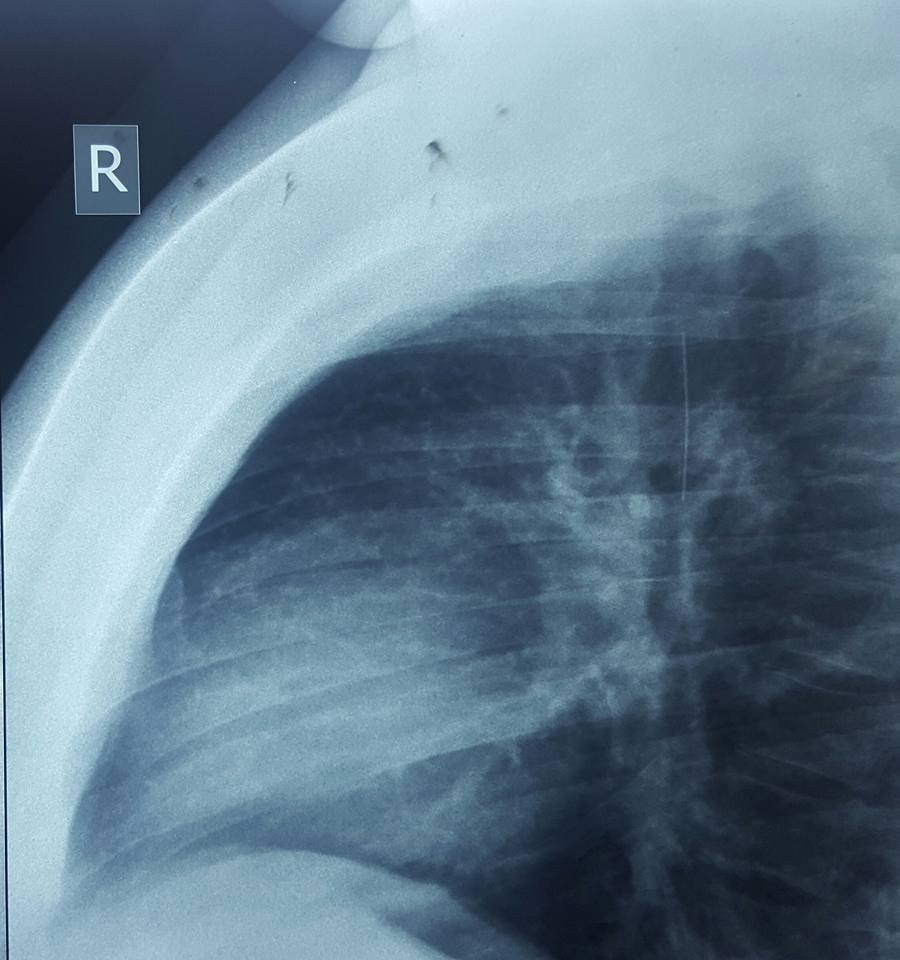

وقال رئيس الفريق الاستشاري في جراحة الصدر والقلب والأوعية الدموية بكلية طب الأنبار، الطبيب محمد طفش، اليوم الجمعة (12 مايو/ايار 2017)، إن "عملية ناظورية اجريت لشاب يبلغ من العمر 16 عاما في مستشفى الفلوجة التعليمي وبمشاركة كادر طبي متخصص، تم خلالها استخراج دبوس من القصبة الهوائية للشاب الفلوجي من خلال عملية استئصال ناظورية دون تدخل جراحي وتكللت العملية بالنجاح التام".

وذكر طفش انه "بعد التشخيص الدقيق لحالة المريض وتحديد مكان استقرار الدبوس من قبل الفريق الطبي وبإشراف طبيب التخدير نزار حامد العبيدي، تم اجراء العملية بنجاح وقد استغرقت ساعة واحدة فقط بعملية ناظورية دون تدخل جراحي"، مضيفا "ان المريض يتماثل للشفاء بعد خروجه من صالة العمليات".